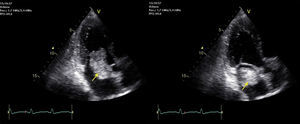

Se realizó un electromiograma que evidenció una mononeuritis del tibial posterior izquierdo sin patrón miopático. Para descartar anormalidades arteriográficas se solicitó una angiotomografía toracoabdominal con contraste. Se administraron glucocorticoides (metilprednisolona 60mg en 2 dosis) por probable alergia al contraste, lo que comportó una mejoría notable de la sintomatología. En la prueba de imagen se objetivó un defecto de repleción intracavitario a nivel auricular izquierdo, por lo que se realizó una ecocardiografía transtorácica que determinó la presencia de una tumoración en la aurícula izquierda de gran tamaño, pediculada, adherida al tabique interauricular a nivel de la fosa oval que prolapsaba en diástole hacia el espacio valvular y que asociaba una ligera insuficiencia mitral (fig. 1).